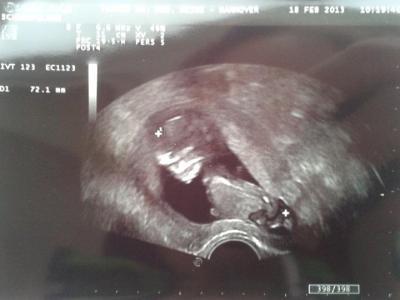

So, nachdem ich eben Schlaf nachgeholt habe, berichte ich mal vom Gyn- Termin :-) Klaus- Bärbel ist schon 7,2 cm groß und so morgenmuffelig wie Papa- ersie hat versucht den Schallkopf mit seinen Füßen wegzuschieben, wir hatten jedenfalls des Öfteren nur die Fußabdrücke auf dem Bild. Ansonsten ist er ein Bauchschläfer/ lieger, mit dem Kopf voll an die Wand gequetscht- wie Mama :-) Ersie hat auch kurz gewunken bzw sich die Augen gerieben oder so :-) ich finde ich habe ein sehr hübsches Kind :-) Ansonsten ist alles tutti- mein Eisenwert steigt und ich habe 1 kilo weniger als vor 4 Wochen, obwohl ich mich mindestens 4 kilo fetter fühle und mich deshalb zu Haus nicht auf die Waage getraut habe :-)

Bild zu Gyn- Termin :-) - Forum für August - Mamis